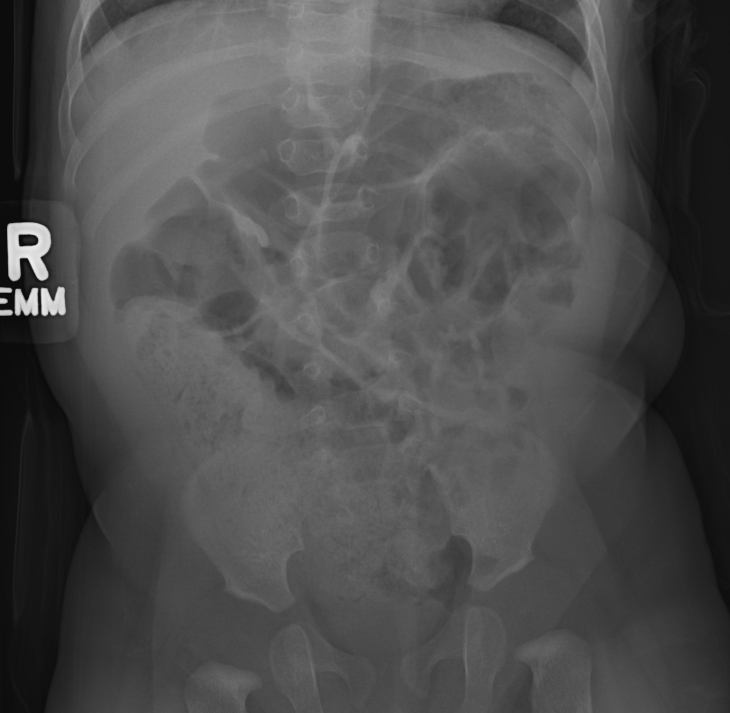

Peds Abdomen

Practice

Simulates call by including subtle or difficult cases and some normals.

30 cases